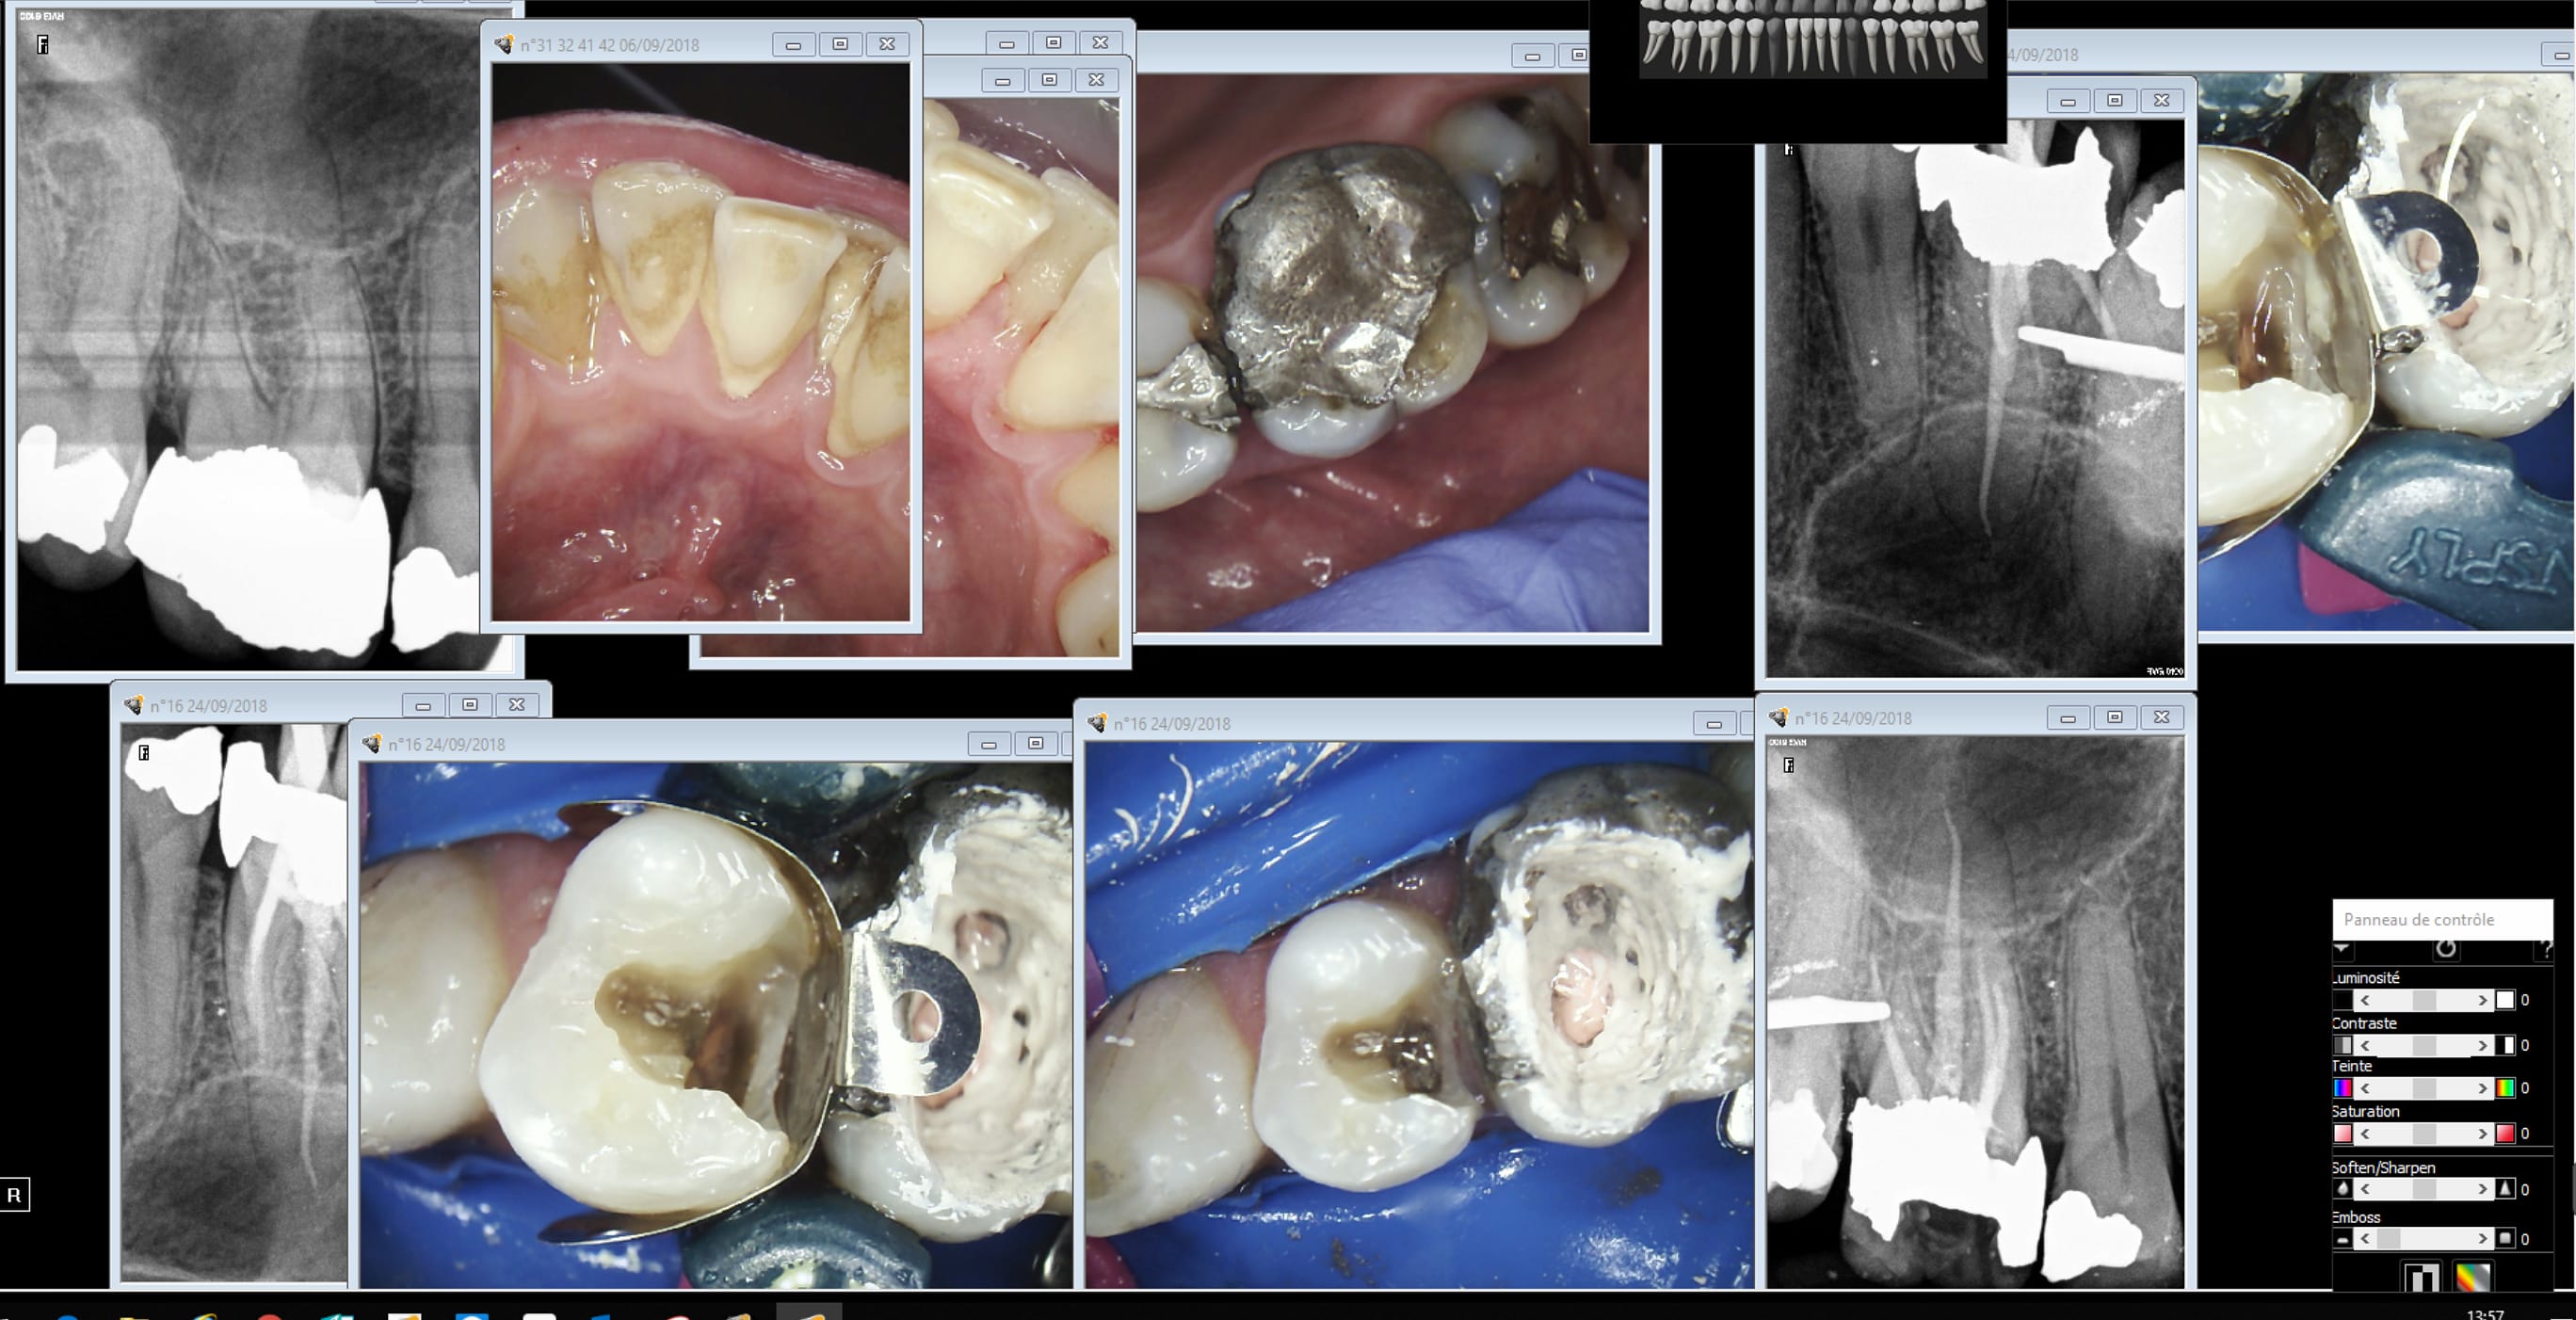

Séance précédente endo compo détartrage.